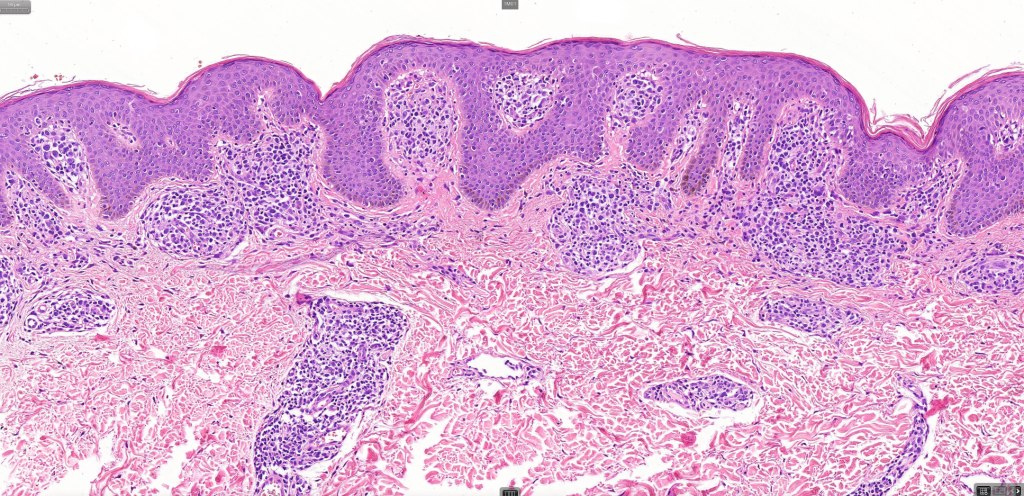

Histological features

•Variable histological features ranging from a non-specific superficial perivascular or band-like dermal infiltrate with minimal or no epidermotropism through to mycosis fungoides-like histology; can mimic atopic dermatitis